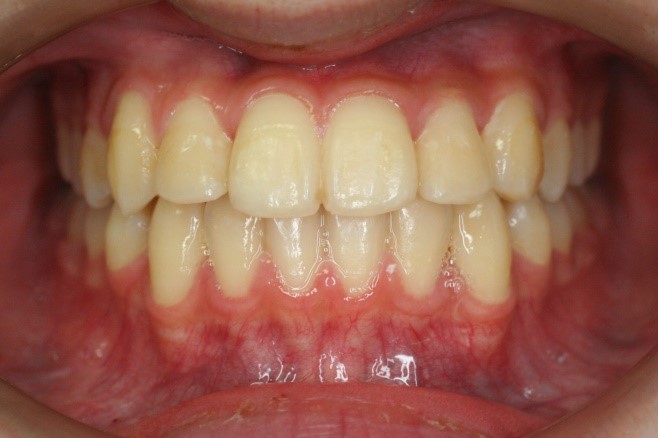

治療後

• 矯正治療後の横顔

• 正面

治療前の写真を治療後の写真を比べると、鼻の下がくぼんでいたのが改善されて口元が綺麗になった事が解ります。また歯並びは綺麗に並び上の歯が前に出て下の歯が後ろに移動して歯がしっかりと咬み合っています。

患者様に協力いただけたため、2年の治療期間で終了することができました。